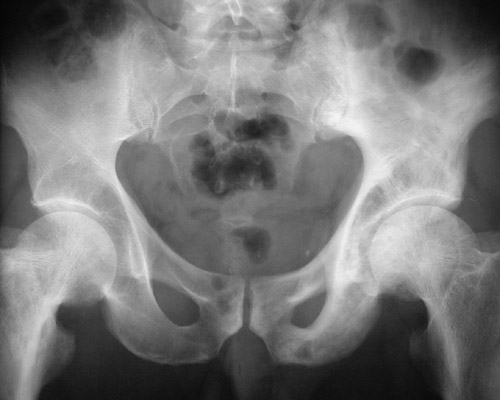

In this example of Paget's disease of bone, there is more extensive bony sclerosis in the region of the hip joint on the left This is the middle to late phase with much osteosclerosis, but also some osteolysis with lucency of the bone.